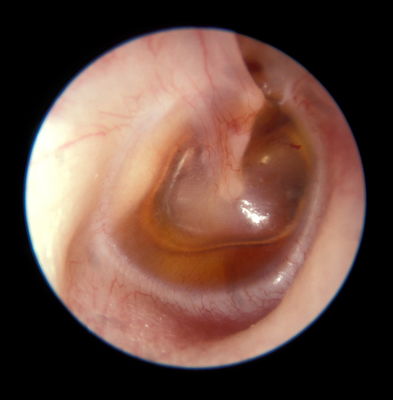

tipo de otitis que se observa en la imagen.

Answer

• otitis media serosa

• otitis media purulenta

• otitis media mixta